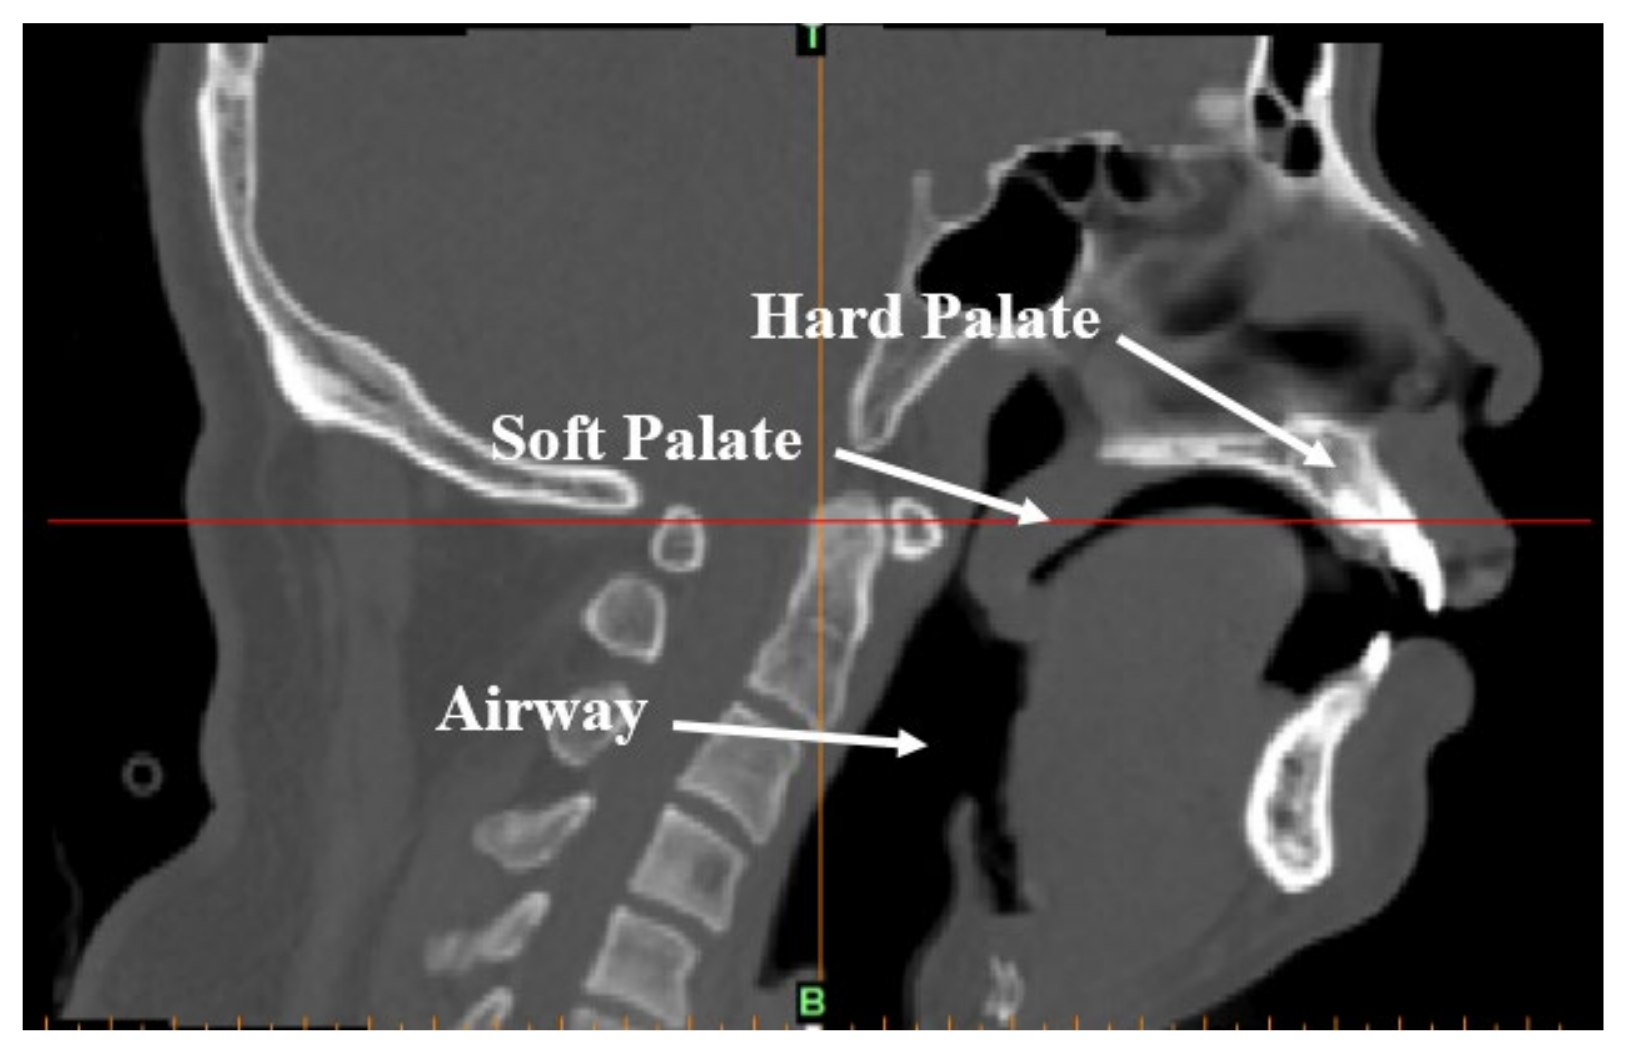

2.1.1. Clinical CT Data and Establishment of Finite Element Model

2.2.1. One-Way Valve Structure of the Soft Palate